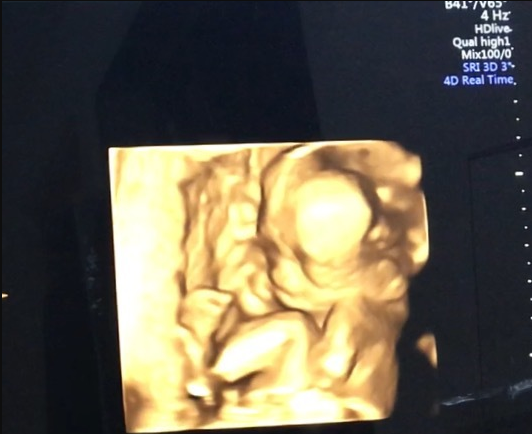

18週1日(18w1d・性別不明)|ぴーさよ さん(30歳)

エコー写真撮影時のエピソード:

初めての4Dエコーでした。 いつも見てるエコーとは違い立体的に見えて愛しさが増しました(^^) 他の人がこれを見たらただのホラー写真ですが。

少し恥ずかしいのか横を向いて隠れようとしていました!正面ではないけどお口をパクパクと動かしてくれて元気一杯で先生にも順調ですねと言われとても安心したのと、ほんとにお腹にいるんだなぁーって改めて思いました(^^)